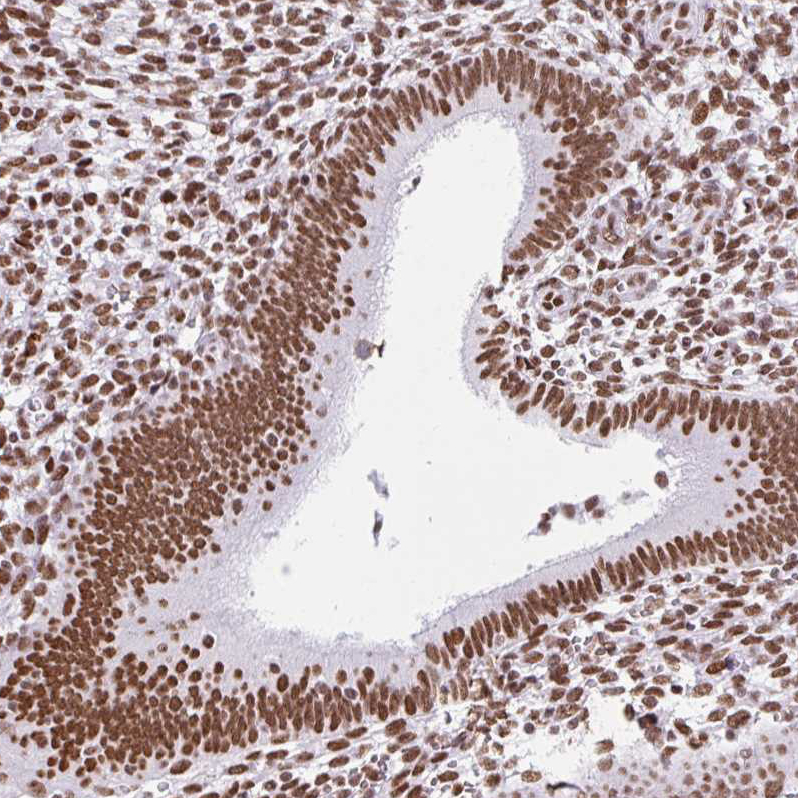

Immunohistochemical staining of human endometrium shows strong nuclear positivity in glandular cells.